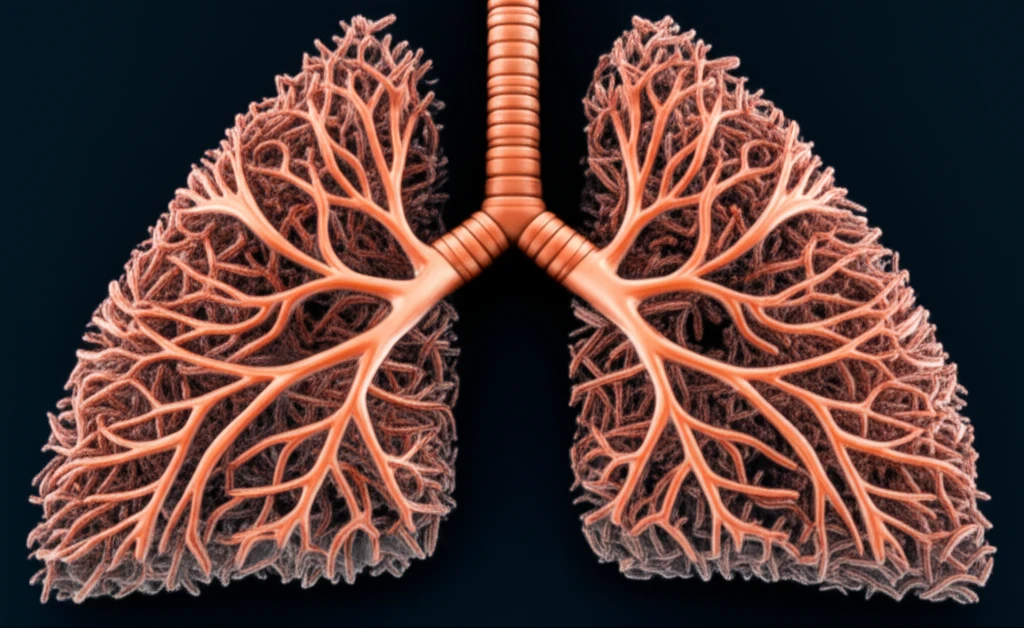

Clostridium difficile (C. difficile) is a bacterium most often associated with infections of the gut, causing symptoms like diarrhea and colitis. Typically, C. difficile infections occur after antibiotic use disrupts the natural balance of bacteria in the intestines. However, in very rare instances, C. difficile can manifest outside the gastrointestinal tract, leading to severe conditions like empyema—an accumulation of pus in the space between the lung and the surrounding membrane.

A recent case report published in Case Reports in Gastroenterology details an unusual occurrence of C. difficile causing empyema in a 42-year-old Hispanic male. This case is particularly noteworthy because the patient had no prior history of C. difficile infection, making the diagnosis challenging and emphasizing the importance of considering extraintestinal manifestations of common pathogens.

This article explores the details of this case report, shedding light on how C. difficile can cause lung infections, the potential mechanisms behind such rare occurrences, and what healthcare professionals and the public need to know about this unusual presentation of a common infection.